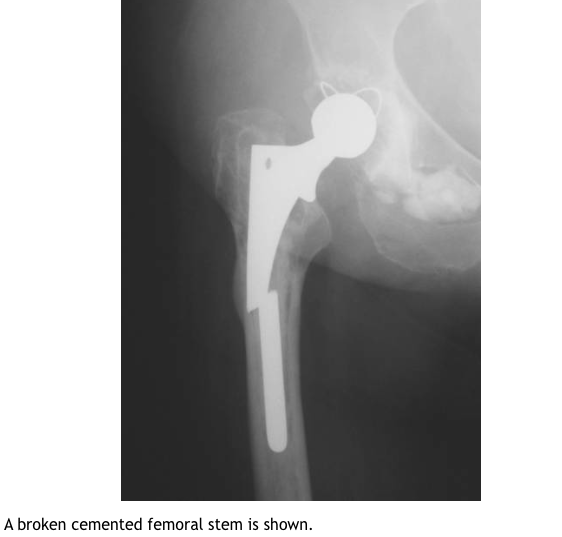

Describe the types of cemented femoral stem?

What is the unqiue complications of cemented femoral stems?